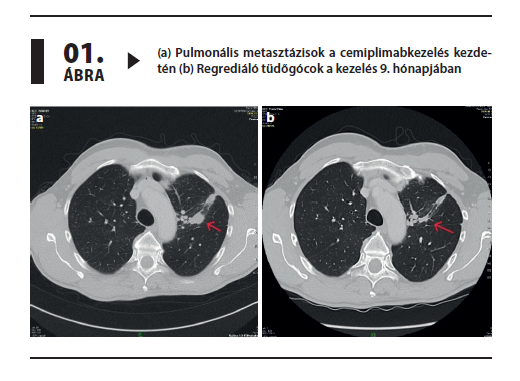

Lokálisan előrehaladott, illetve tüdőáttéteket adó bazálsejtes karcinóma szisztémás kezelése